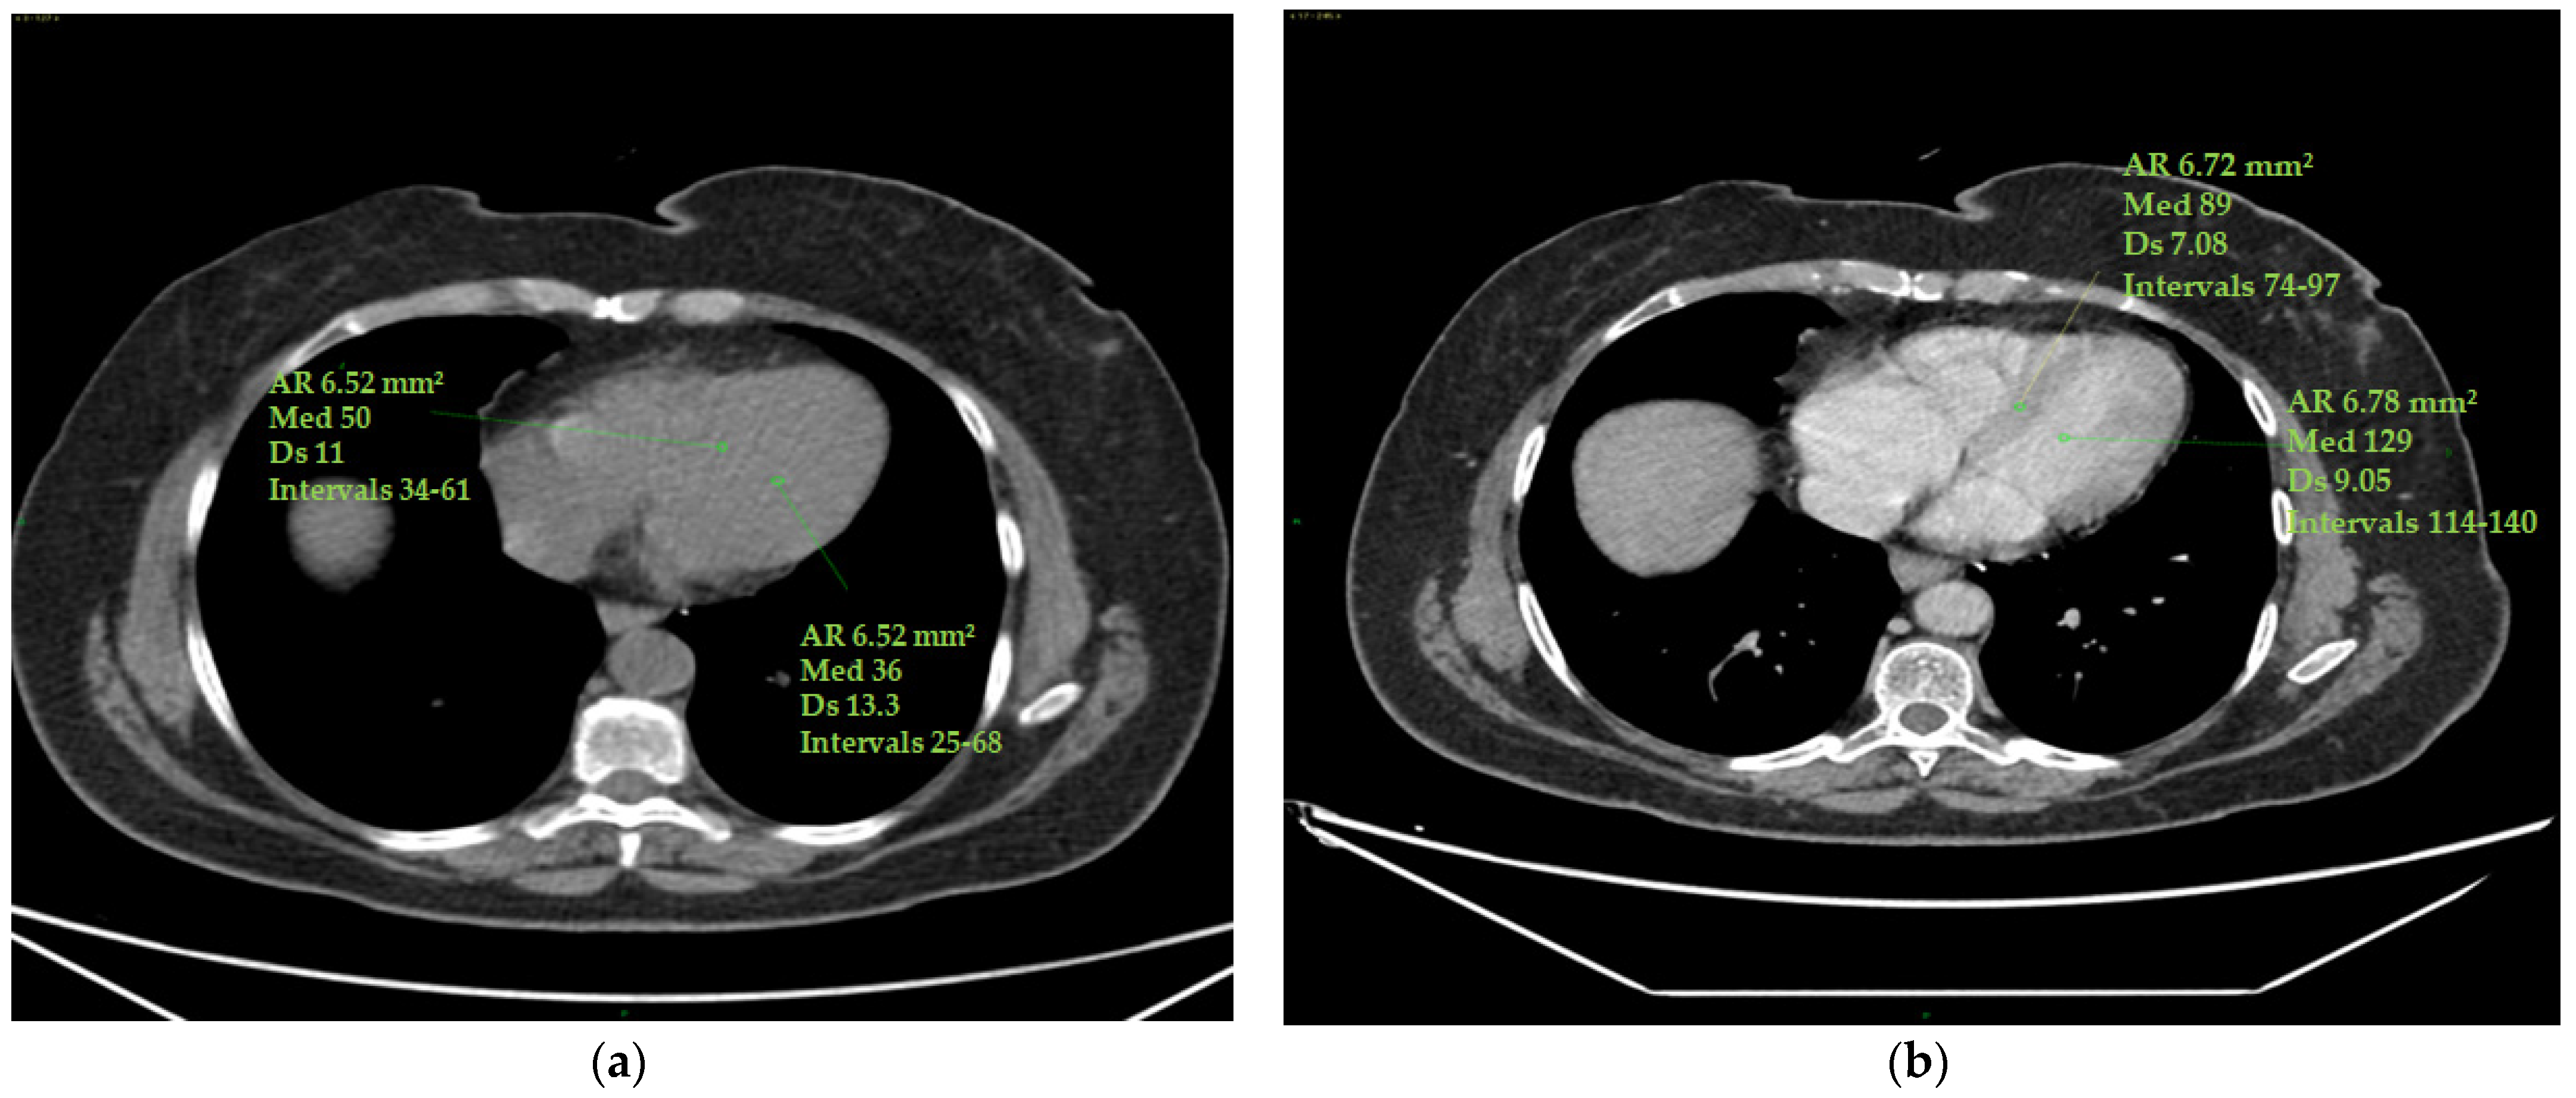

To calculate the ECV, the operator selected the optimum slice to observe the four cardiac chambers from an axial perspective.

The measurements were taken by manually inserting one ROI in the left ventricle’s ‘blood’ pool and a second ROI in the middle of the interventricular septum, avoiding papillary muscles. The same ROIs were set in the pre-contrast and post-contrast scans (portal phase). ROIs were measured in two stages (basal and portal) at time 0 and at the end of chemo-immunotherapy to provide Hounsfield units (HUs) to be used in the ECV calculation.

Standard deviations of ROIs were calculated to avoid contamination of myocardial HU measurements by motion artefacts. Altered values were not considered in this study (Figure 1).

Figure 1.

ECV measurement. Myocardial and blood pool HU values were obtained on the four cardiac chambers’ projection from an axial perspective on CT scans by manually inserting one ROI (with a mean area of 6 mm2 ca) in the middle of the interventricular septum and a second ROI (with a mean area of 6 mm2 ca) in the left ventricle’s ‘blood’ pool. Papillary muscles were avoided. The ROIs were set to the same level both in the pre-contrast scans (a) and in the post-contrast scans (at portal phase) (b). ROI standard deviations were calculated to avoid contamination of myocardial HU measurements by motion artefacts. The figure shows an example of the area of the region of interest (Ar ROI), the mean (med), the standard deviation (Ds) and the range(intervals) of hounsfield units measured.